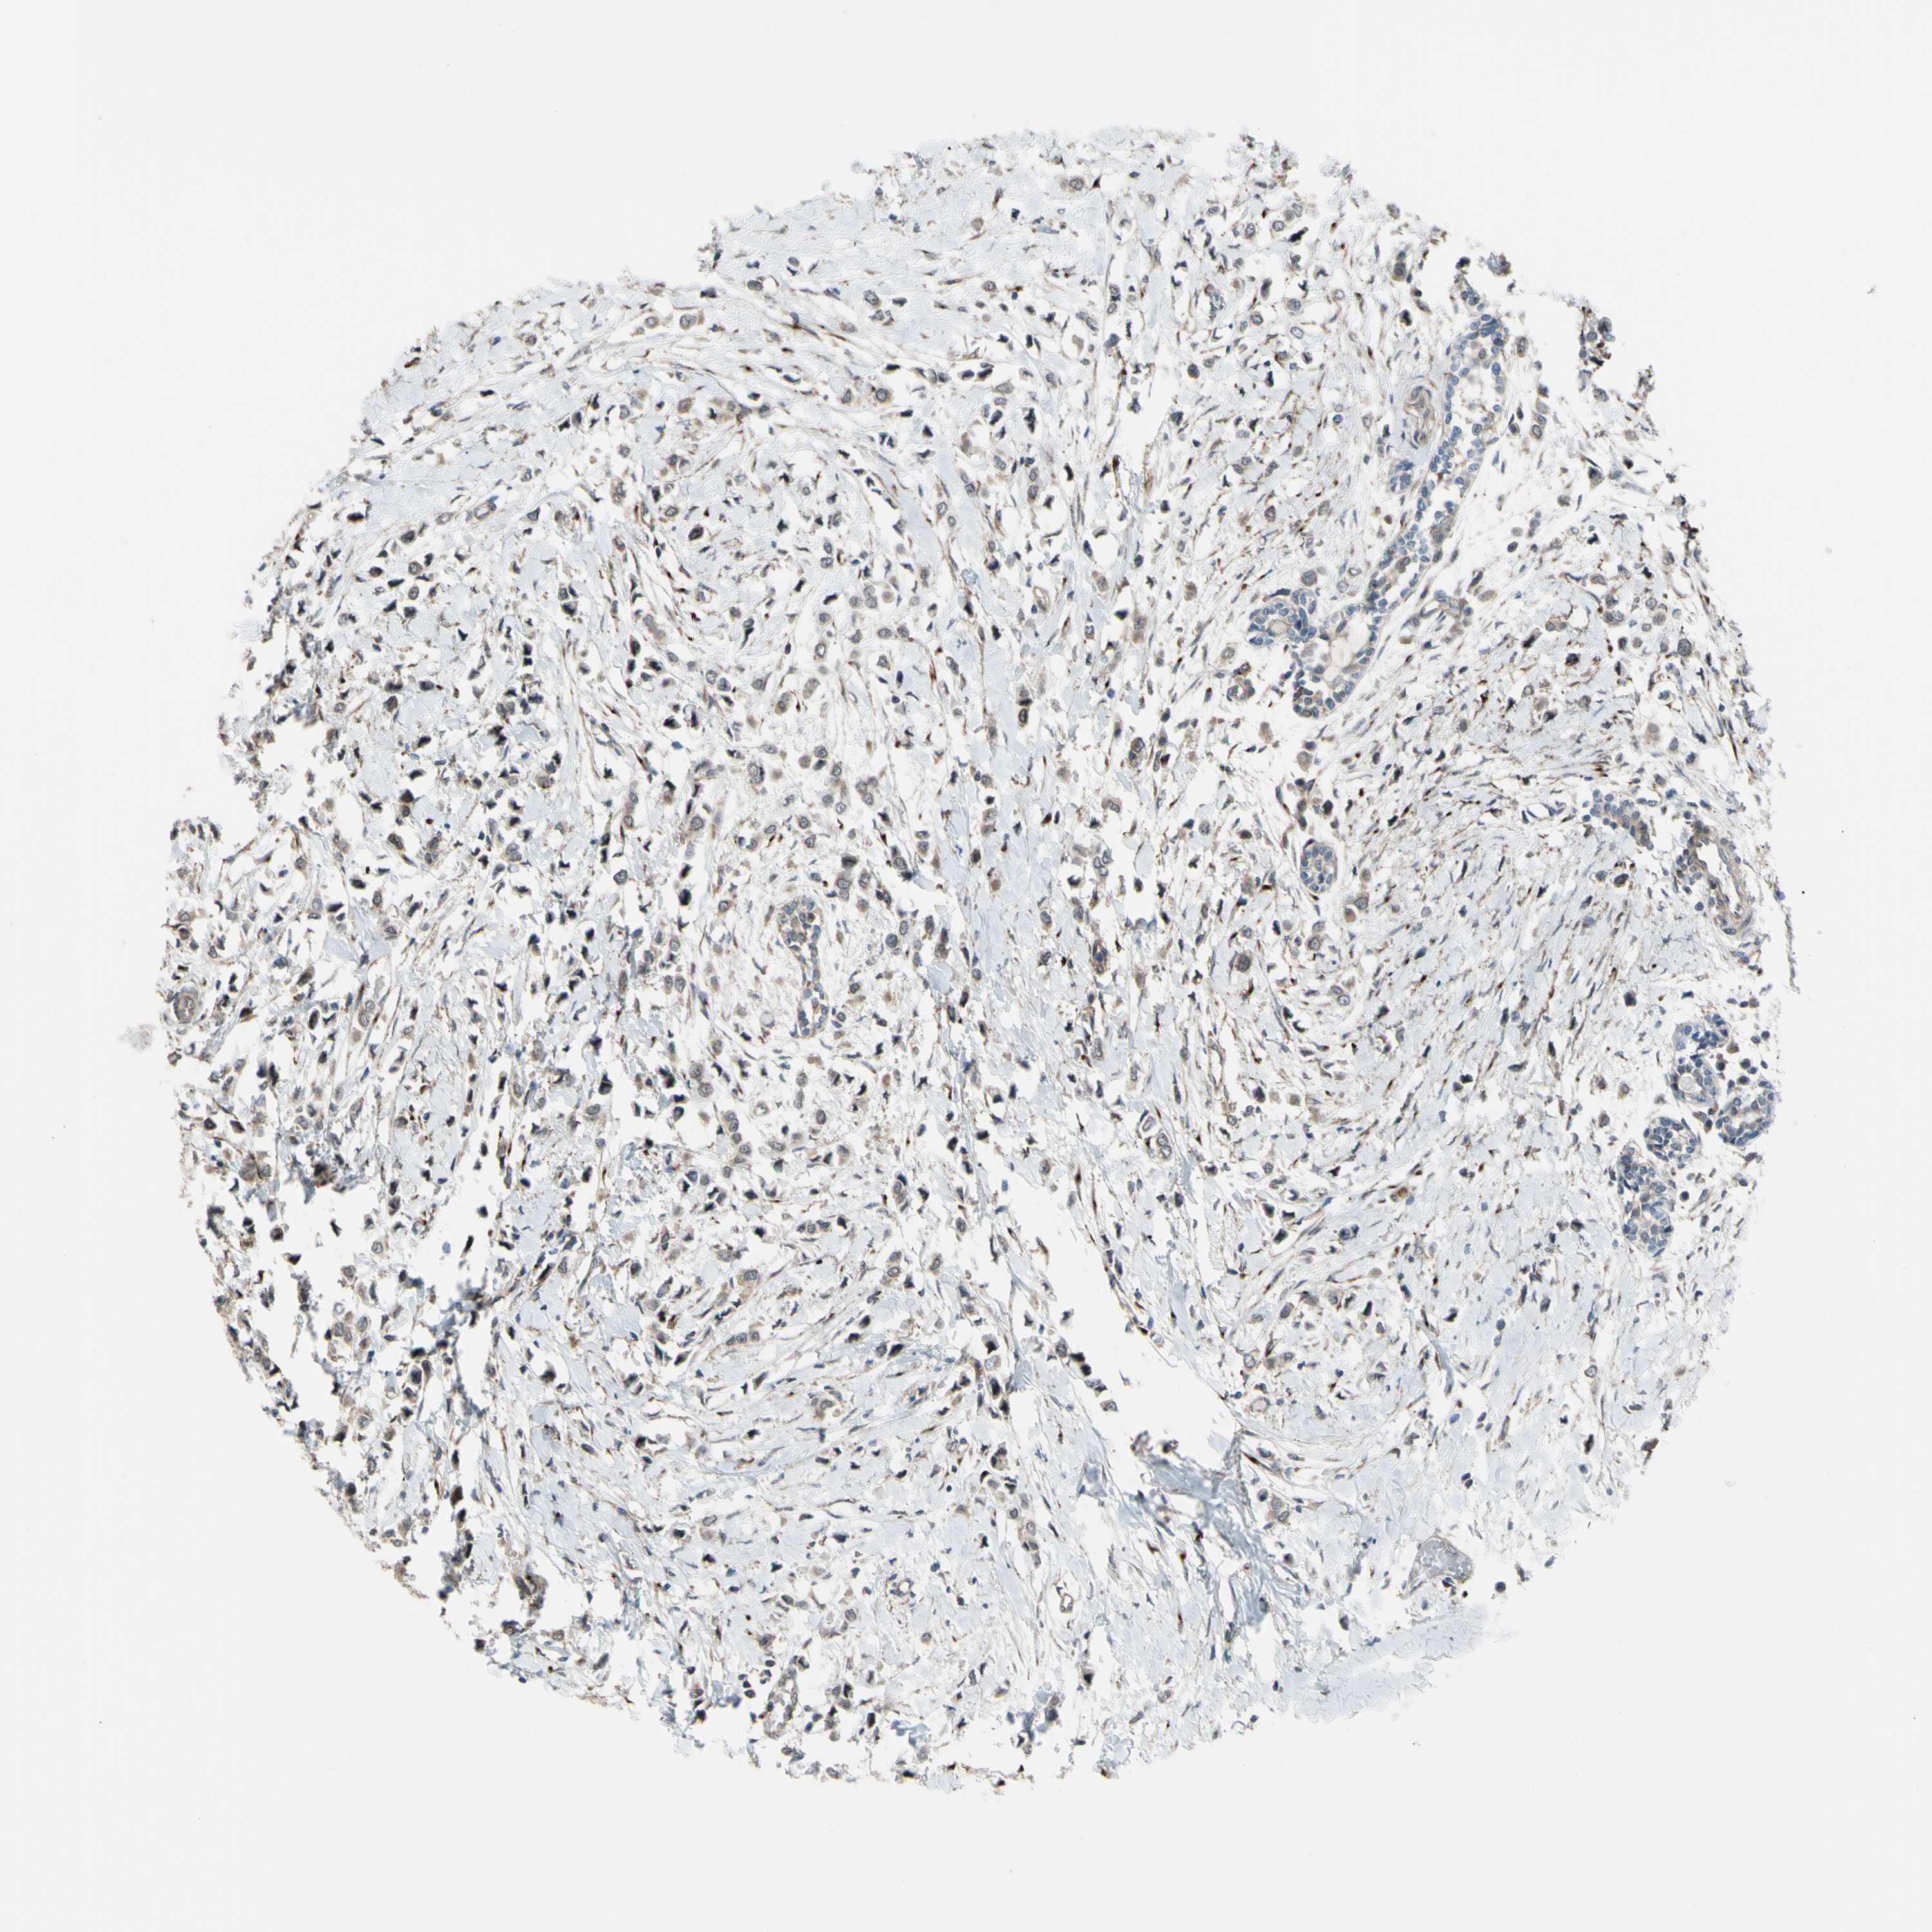

CANCER BREAST CANCER Show tissue menu

BRCA TCGA BRCA VALIDATION PROTEIN EXPRESSION